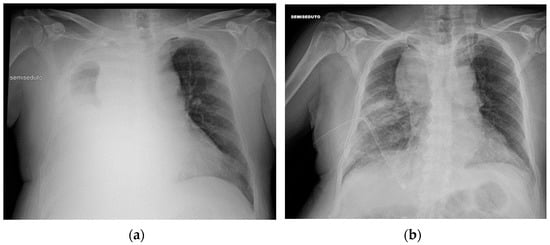

3.1. Central Vein Catheter (CVC)

3.2. Peripherally Inserted Central Catheter (PICC)